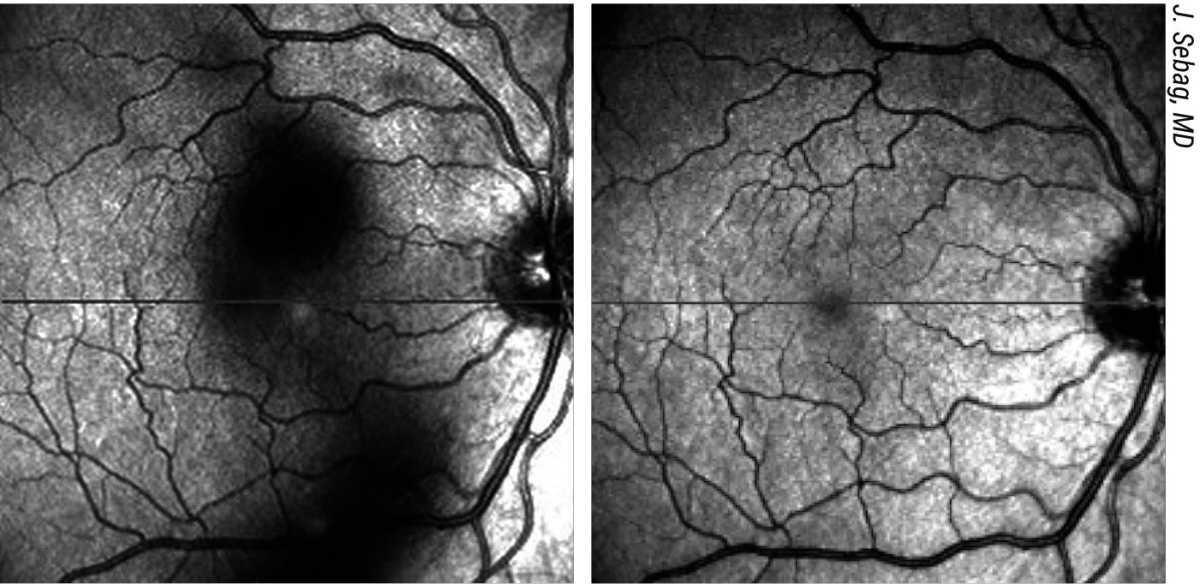

Figura 4. Las opacidades del cuerpo vítreo proyectan sombras sobre la retina (imagen a la izquierda) que los pacientes perciben como "moscas volantes". Éstas se desplazan con el movimiento de la cabeza y las sacadas oculares, mostrando una dinámica de movimiento característica ("retraso" y "rebote") debido a las propiedades viscoelásticas del vítreo. Tras una vitrectomía limitada, el vítreo central está limpio (imagen a la derecha), cesan los síntomas de moscas volantes y se normaliza la sensibilidad al contraste.6-8